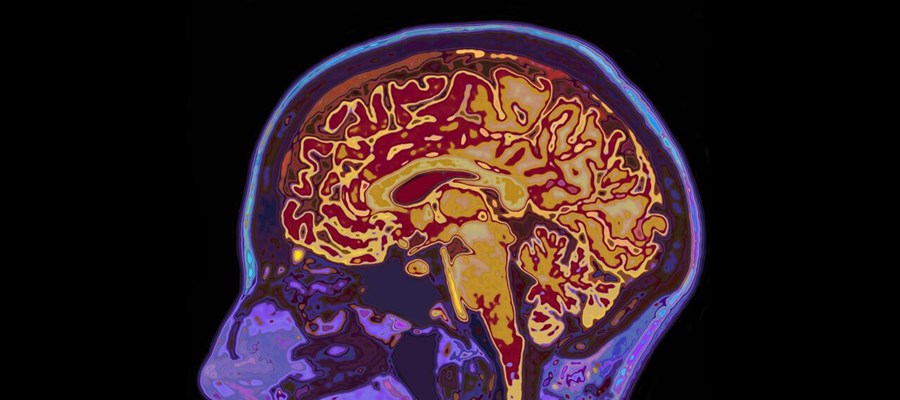

Med ett AI-verktyg har forskare vid Karolinska Institutet analyserat hjärnbilder från 70-åringar och skattat hjärnans biologiska ålder. Faktorer som påverkar kärlen negativt, som inflammation eller högt blodsocker, kunde kopplas till att hjärnan såg äldre ut, medan hälsosam livsstil var kopplad till hjärnor med yngre utseende. Resultaten är presenterad i Alzheimer's & Dementia: The Journal of the Alzheimer's Association.

I studien ingick 739 kognitivt friska 70-åringar, varav 350 män, som var rekryterade inom Göteborgskohorten H70. Allas hjärnor avbildades med magnetkamera och utifrån bilderna skattades hjärnans ålder med hjälp av en AI-baserad algoritm som forskargruppen har utvecklat.

– Algoritmen är både exakt och robust, men samtidigt enkel att använda. Detta är för tillfället ett forskningsverktyg som behöver utvärderas ytterligare men målet är att den framåt ska kunna användas även kliniskt, exempelvis i samband med demensutredningar, säger Eric Westman, professor i neurogeriatrik vid samma institution, som har lett studien.